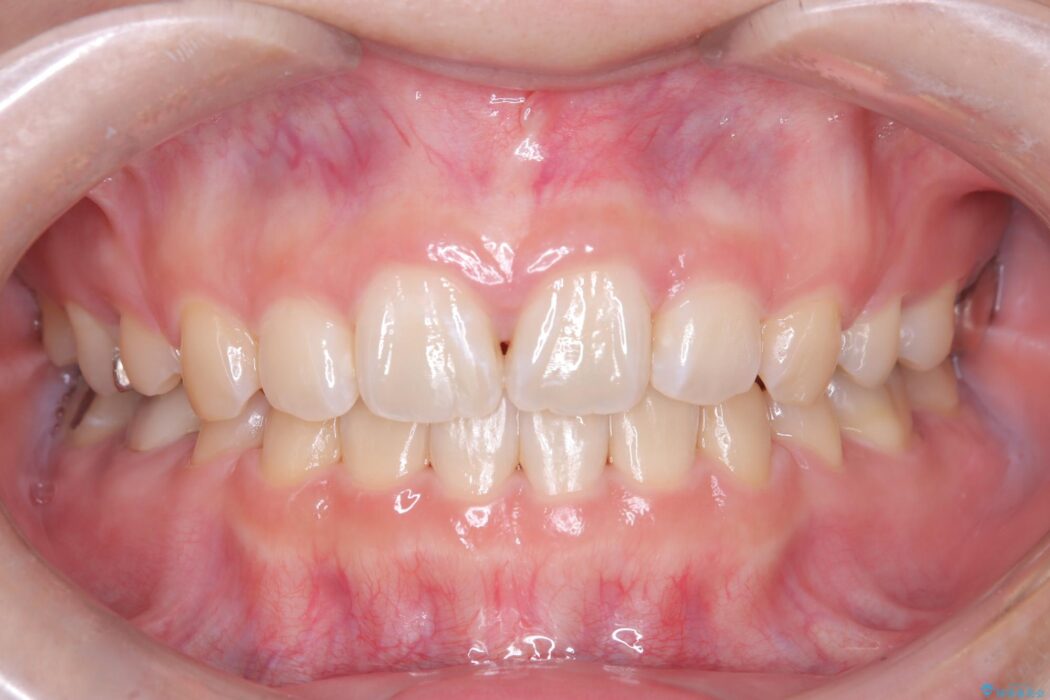

口元が突出していることを気にされご来院された患者様です。

装置には、上顎には目立たない裏側矯正(舌側矯正)を、下顎には透明な審美ブラケットを使用するハーフリンガル矯正を採用しました。抜歯によってできたスペースを最大限に活用し、前歯を効率よく後方へ移動。治療の結果、口元の突出感が大幅に解消され、Eライン(横顔の美しさの基準)も改善しました。人目を気にすることなく治療を完遂し、自信の持てる美しい横顔を獲得していただけました。